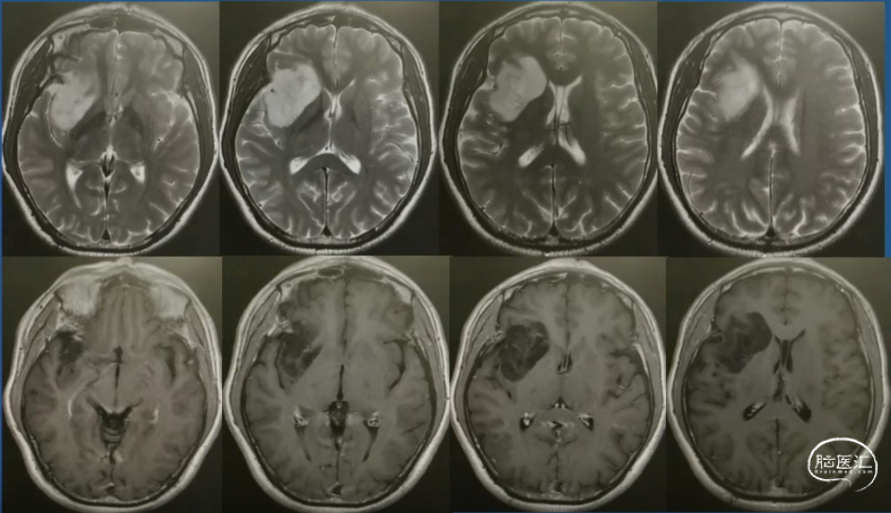

术前影像

术后影像(术后两年)

术前影像

术后三年影像-肿瘤控制良好